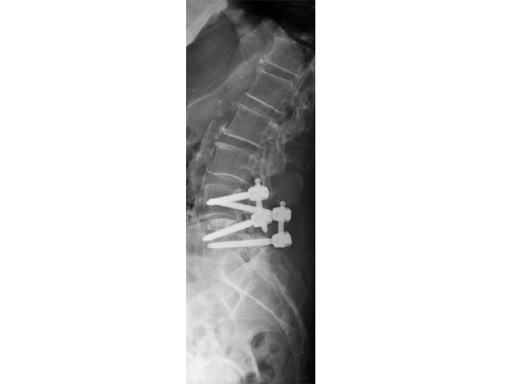

Matrix MIS

This system uses cannulated pedicle screws attached to screw-mounted tissue retractors. This combination allows pedicle screw insertion and rod introduction with minimal tissue disruption. The system is applicable to single and multi-level procedures requiring posterior instrumentation.

Unique to Matrix MIS are cannulated pedicle preparation instruments, screw-mounted tissue retractors and a rod introduction instrument.